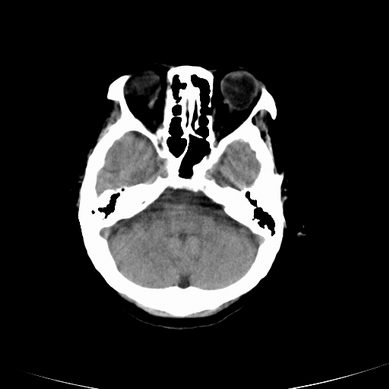

以下是引用jsgdoctor在2008-7-16 23:11:00的发言:[br]左侧大脑中动脉供血区脑梗塞